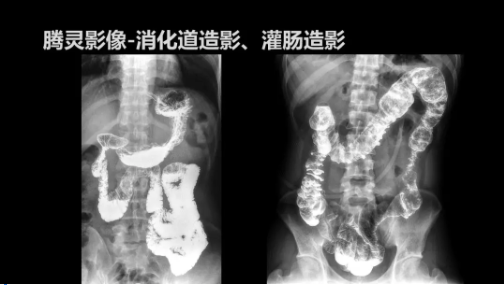

“騰靈”是安健科技的第四代動(dòng)態(tài)DR產(chǎn)品,可實(shí)現(xiàn)全科室應(yīng)用。如各類常規(guī)的X線檢查、消化道檢查、骨科檢查、婦科、兒科檢查等。此外,安健科技為“騰靈”在真正意義上實(shí)現(xiàn)多科室、多功能診斷進(jìn)行了多項(xiàng)針對性設(shè)計(jì)。

此外,“騰靈”為了能夠幫助醫(yī)生更快速、有效的定位病灶,還增加了多項(xiàng)精準(zhǔn)診斷保障功能,如支持動(dòng)態(tài)觀察診斷,實(shí)時(shí)高清點(diǎn)片等?!膀v靈”透視切換高清點(diǎn)片曝光,捕捉關(guān)鍵病灶診斷僅需0.8s,同時(shí)還支持圖像局部放大,醫(yī)生可自由切換15’12’和9’三種放大模式,另外,“騰靈”還支持視頻保存、回放功能,幫助醫(yī)生在檢查結(jié)束后通過回放查看細(xì)節(jié),為醫(yī)生的診斷增加信心。